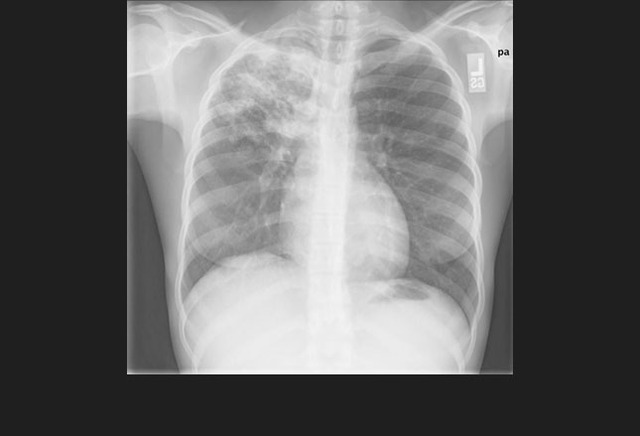

图3. 一位继发性肺结核患者左上叶斑片状实变及空洞形成

影像学特征包括斑片状或肺叶的实变、空洞(继发性肺结核的典型表现)、纵隔淋巴结肿大和胸腔积液。继发性肺结核常侵犯上叶尖后段及下叶背段。代表着血行播散的粟粒型肺结核并不常见,但预后不佳。